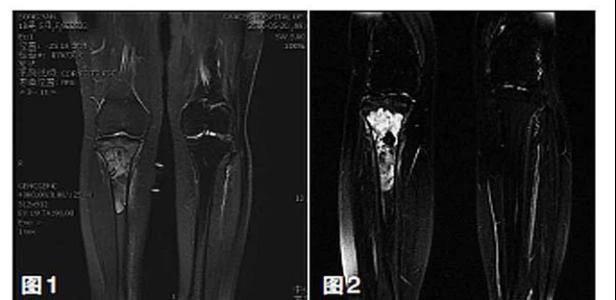

保肢治療指經(jīng)典型骨肉瘤在多學(xué)科團(tuán)隊醫(yī)生共同努力下完成的新輔助化療、保肢手術(shù)和輔助化療等一系列治療總稱,其目的是在提高患者生存率的前提下,減少局部復(fù)發(fā)、盡量保留良好的肢體功能。肢體經(jīng)典型骨肉瘤保肢治療方法如下圖所示:

關(guān)于新輔助化療